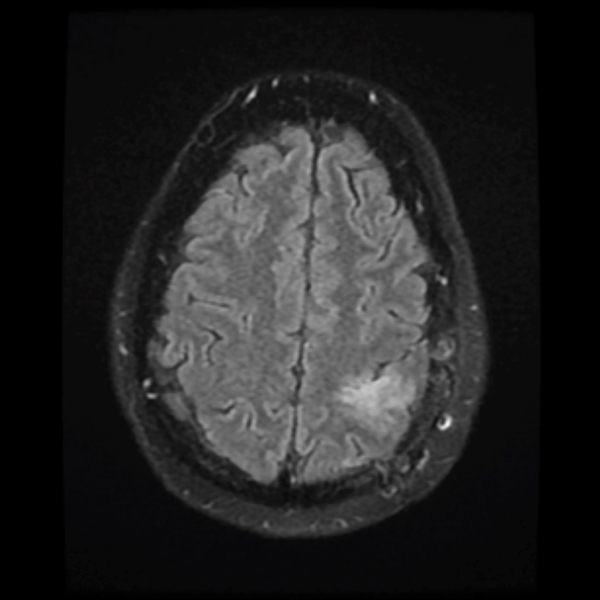

Treatment with chemotherapy and radiation under the care of Dr. Grewal resulted in a durable response of the tumor as evident in the post-treatment images.

The patient has returned to work with a resolution of cognitive impairment, has no neurological impairment, and the tumor continues to shrink on each serial MRI.

December 2019